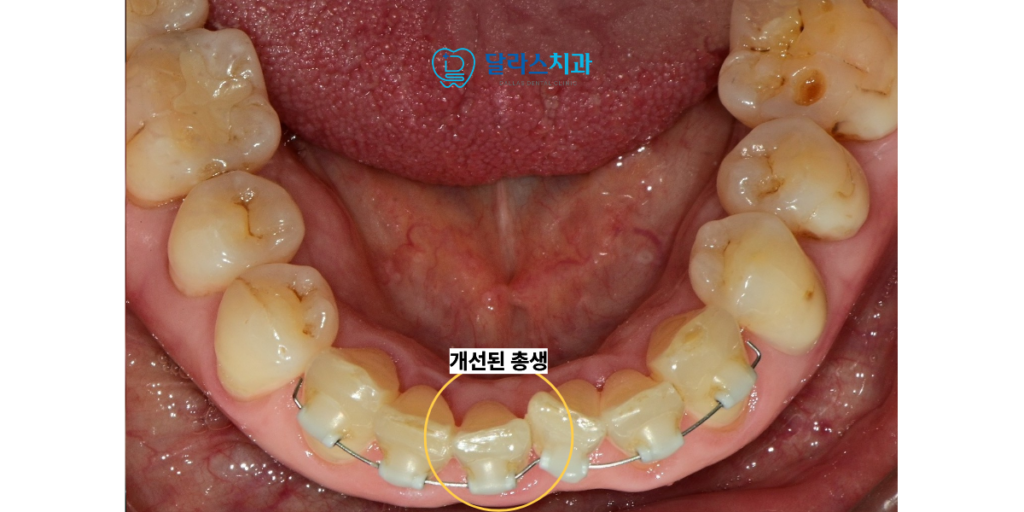

먼저 하악 부위에 교정 장치를 부착하여 겹쳐진 치아들을 가지런히 펴는 작업을 시작하였습니다.

“하악 교정 후 상악 교정까지”

치료가 진행되면서 약 2달만에 하악의 치열이 눈에 띄게 개선되자

환자분께서는 치료 과정과 결과에 대해 매우 높은 만족감을 나타내셨습니다.

하악의 변화를 직접 경험하신 환자분께서는

위쪽 치아인 상악의 문제도 함께 해결하기를 원하셨습니다.